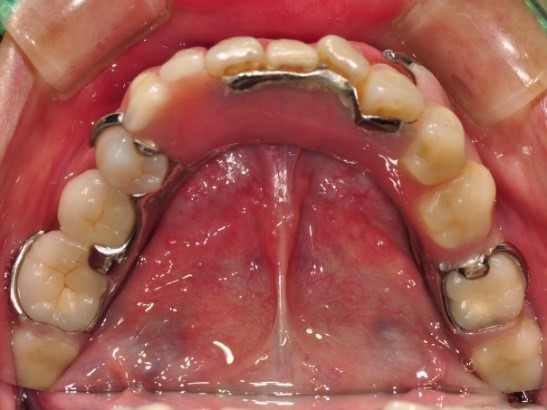

裝上RPD活動式假牙

裝上活動式假牙-上顎